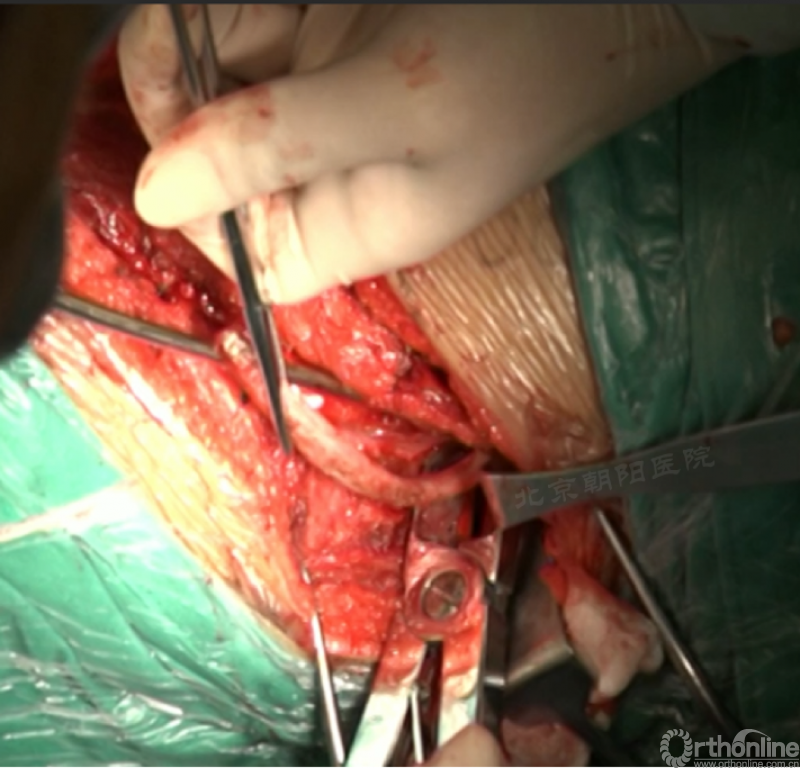

内固定选择的是5.5mm双棒系统,先置入顶椎的螺钉垫板。

置入顶椎的椎体螺钉,螺钉可置入椎体中部到后方1/3之间的范围内。

使用双棒系统时,先置入背侧的螺钉,螺钉指向椎体中线,后置入腹侧的螺钉,螺钉轻度指向后侧。形成对椎体的三角形抓持力。

胸腔侧、腹腔侧螺钉全部置入后,骨移植物植人的越靠近后纵韧带或者纤维环的后缘越好。